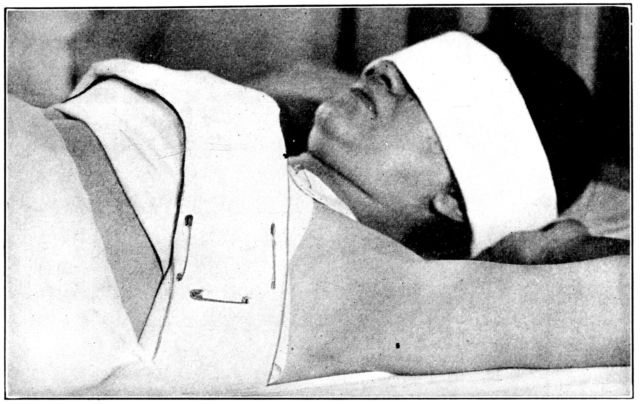

| 125. | Y binder applied | 346 |

| 126. | The same seen from the other side | 347 |